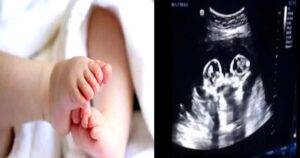

పది నెలల చిన్నారి కడుపులో కవలలు.. ఆశ్చర్యపోయిన డాక్టర్లు..!

సాధారణంగా చిన్నపిల్లలు మామూలుగా ఏడుస్తుంటారు. ఓ 10 నెలల చిన్నారి విపరీతంగా ఏడుపు మొదలుపెట్టడంతో ఆ తల్లిదండ్రులు మొదట్లో సాధారణ ఏడుపే మొదలు పెట్టడంతో ఆ … [Read more...]